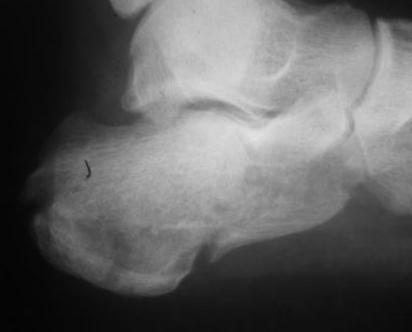

Re: перелом пяточной кости

Из личного опыта, кстати после снятия кортикальной створки, репозицию удобно делать роторасширителем.